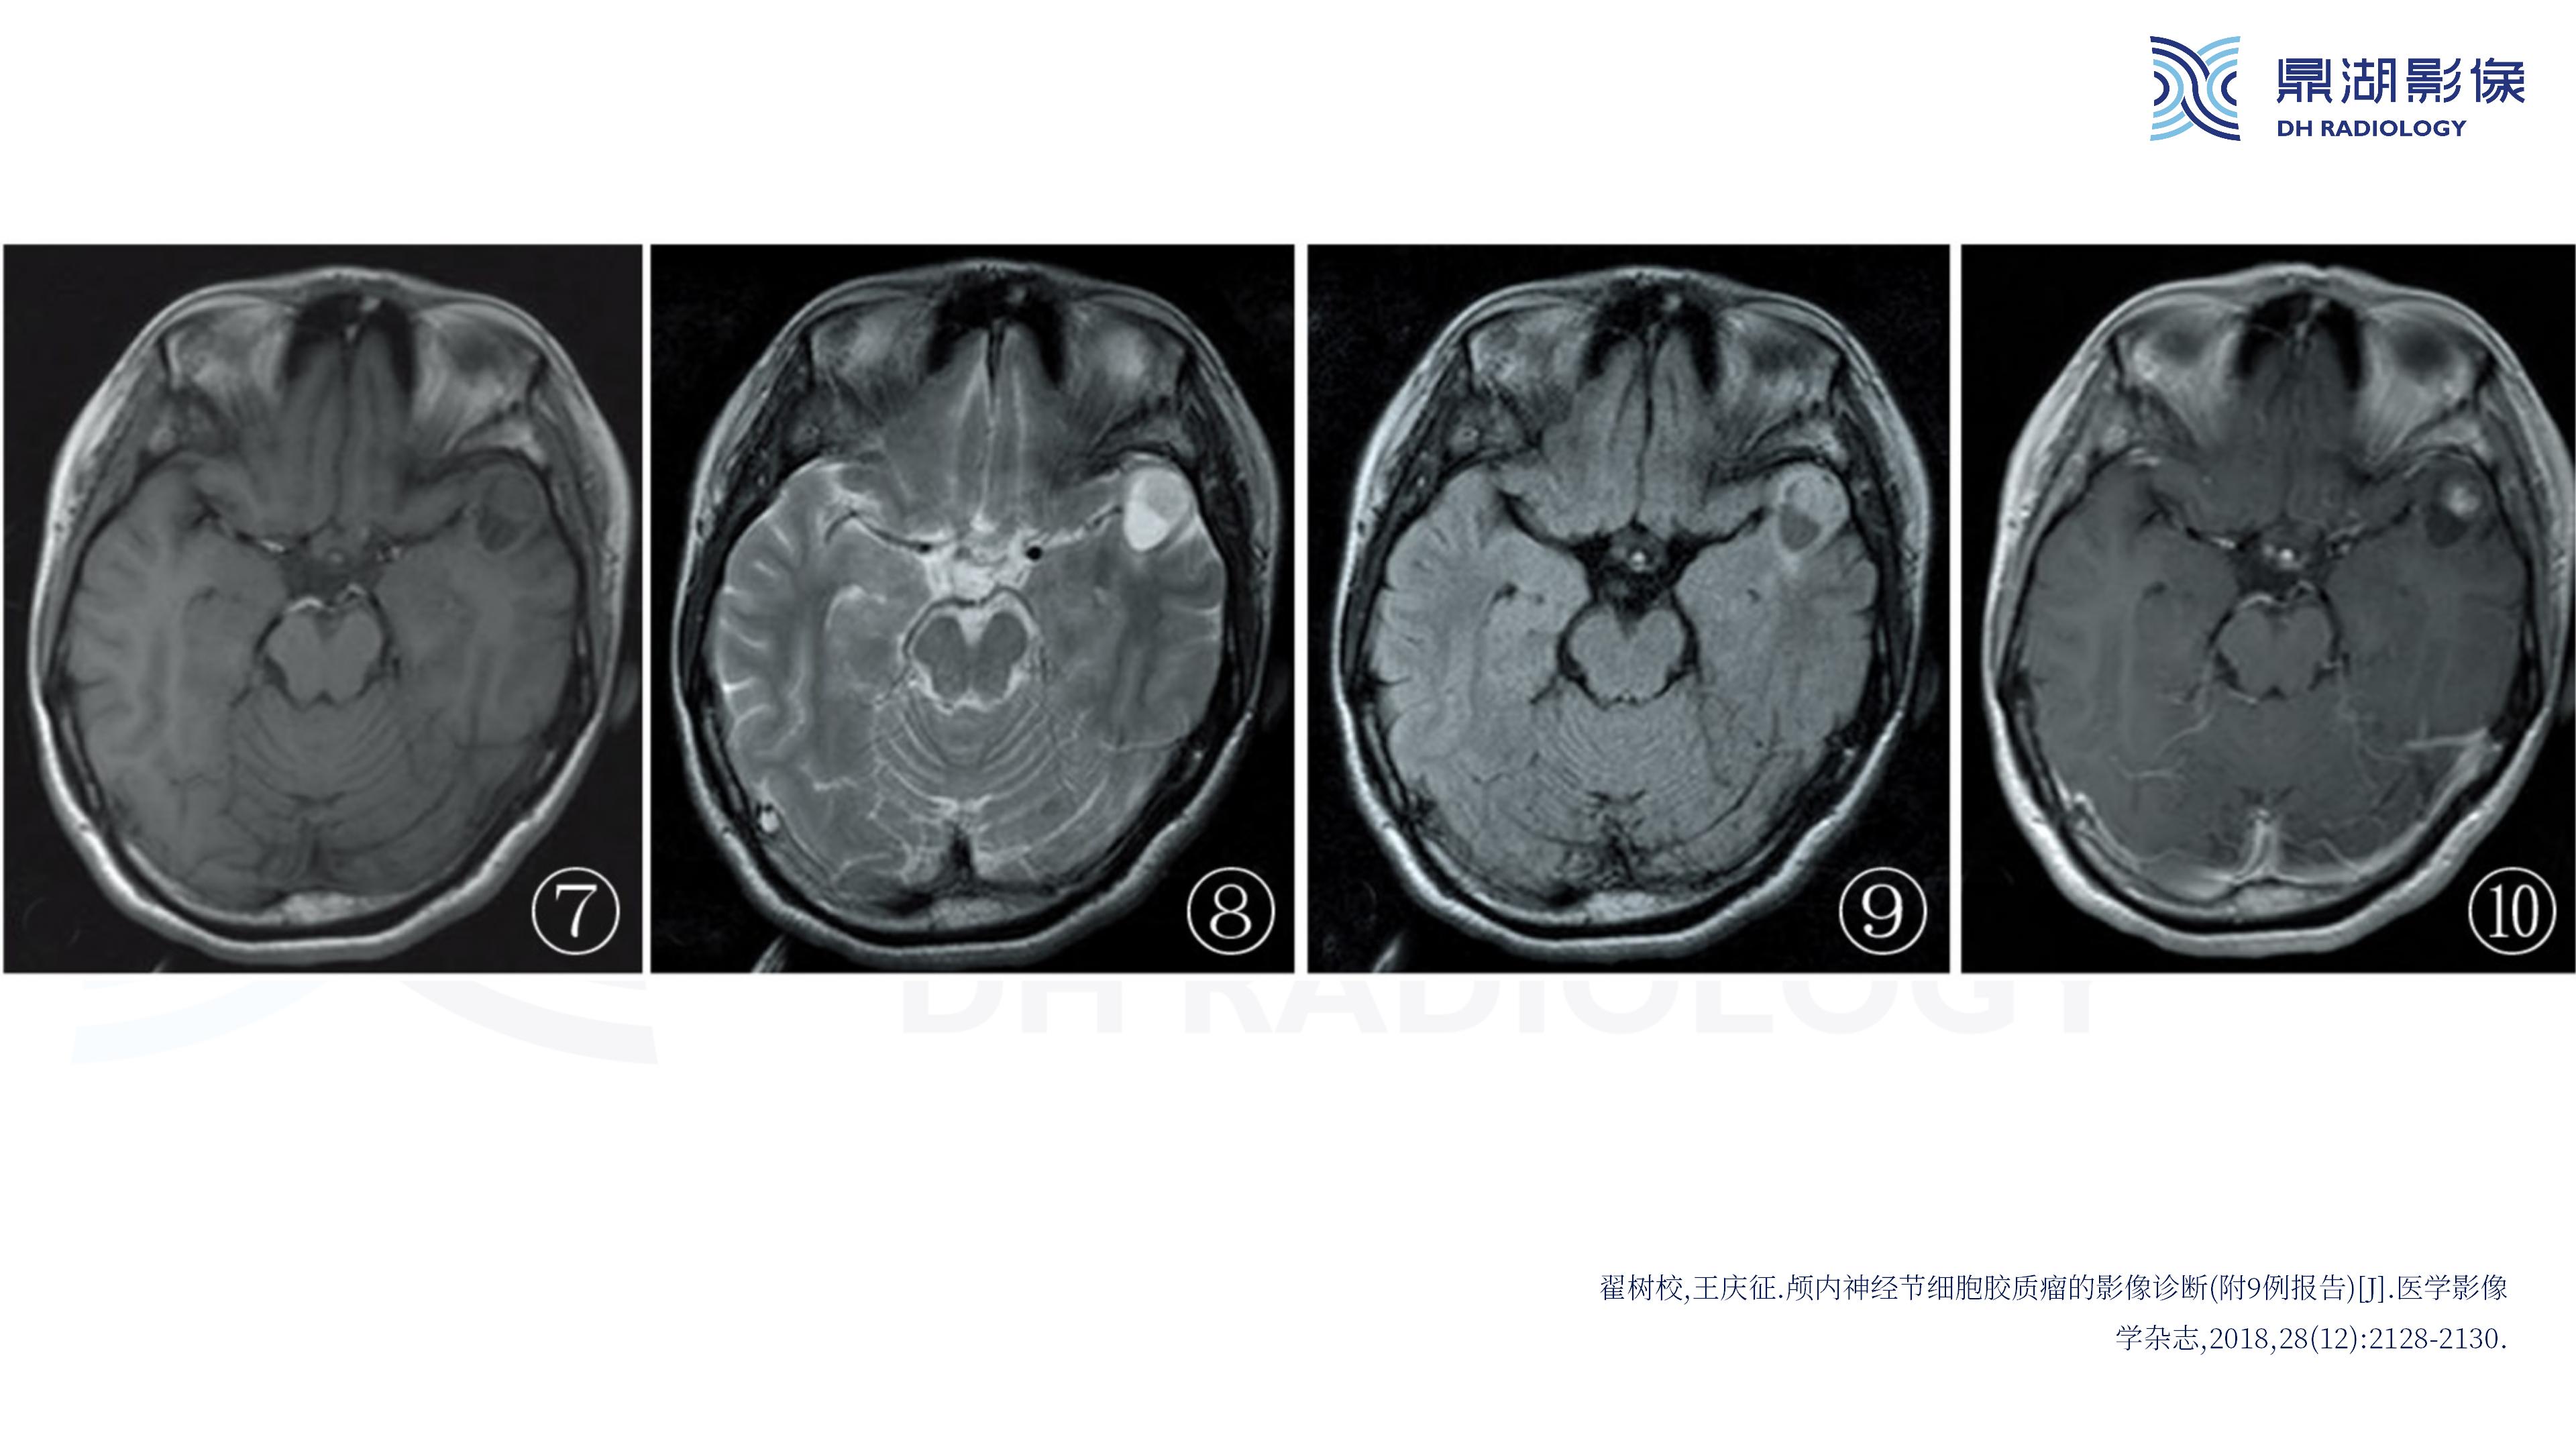

幕上毛细胞型星形细胞瘤(WHO Ⅰ级)